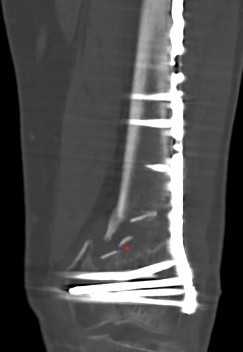

Xray / CT

Options

Dual Plate

Plate + Retrograde nail

Distal femur replacement

Indications

Significant comminution

Loss of medial cortical buttress